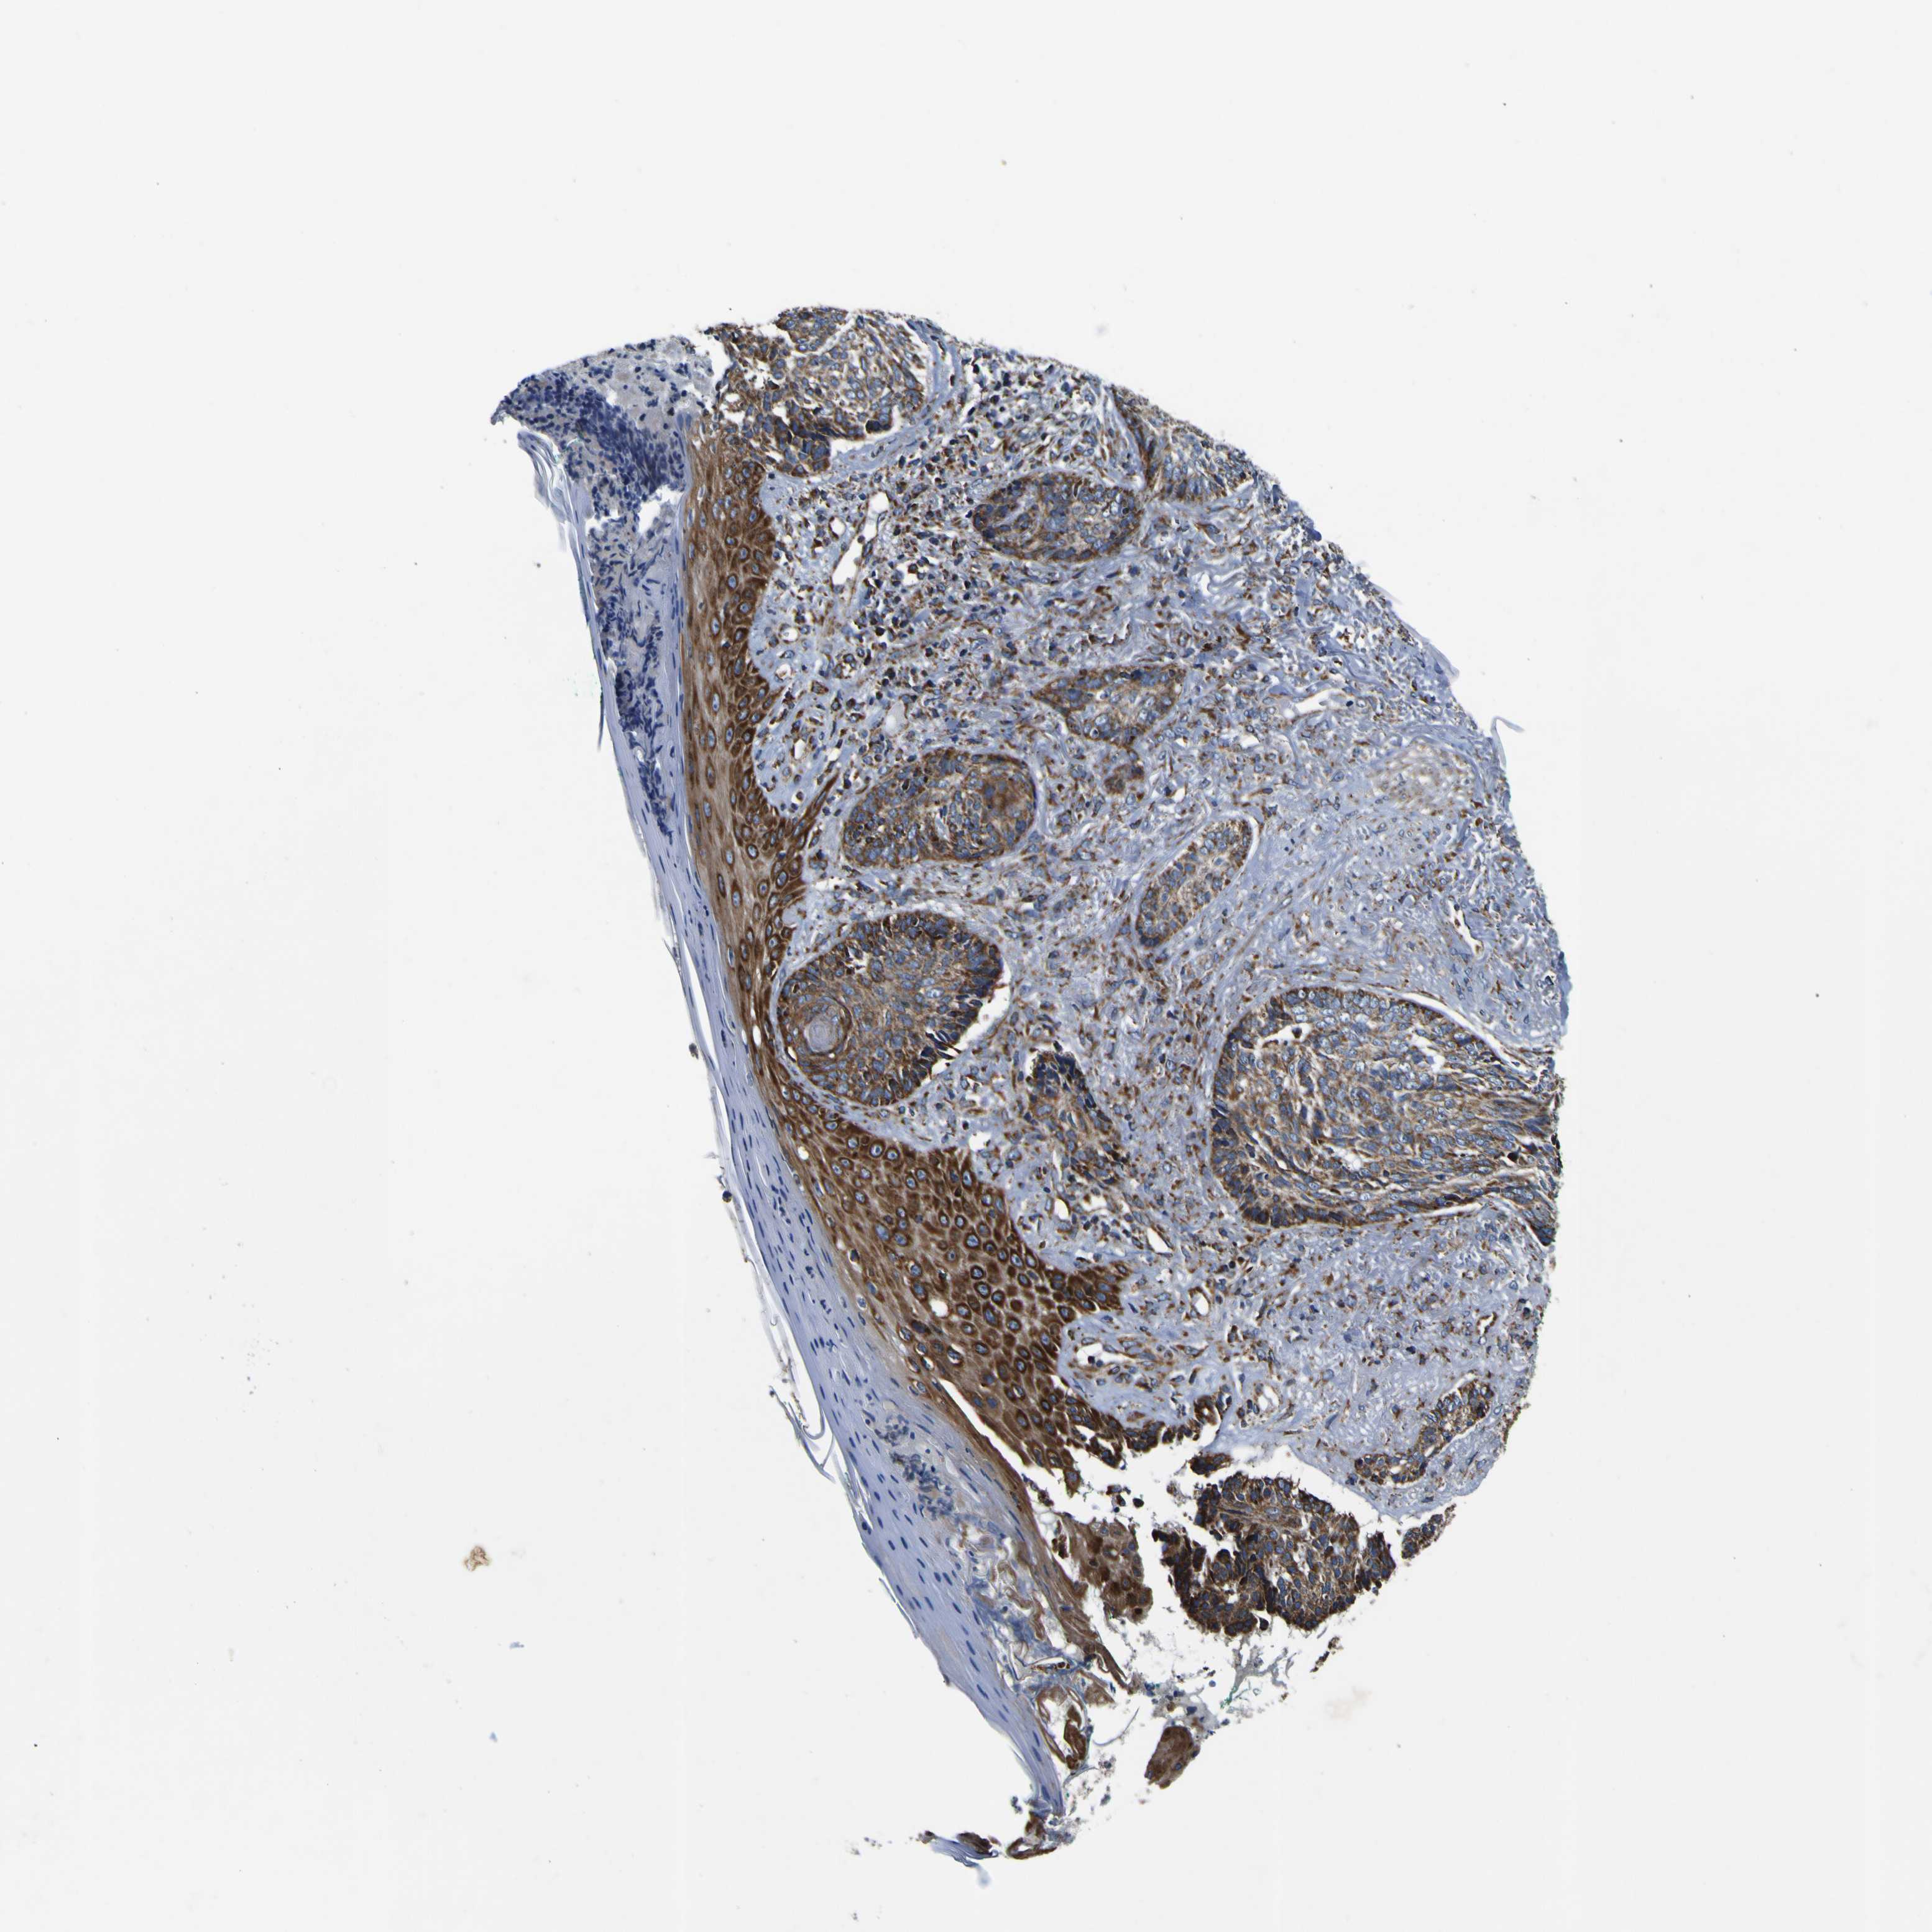

SKIN CANCER - Protein expressioni

A mouse-over function shows sample information and annotation data. Click on an image to view it in a full screen mode. Samples can be filtered based on level of antibody staining by selecting one or several of the following categories: high, medium, low and not detected. The assay and annotation is described here.

Each image is clickable and will lead to virtual microscopy that enables deeper exploration of all samples and also displays staining intensity scores, fraction scores and subcellular localization as well as patient and tissue information for each sample.

Antibody HPA012897

Staining

High

Medium

Low

Not detected

Intensity

Strong

Moderate

Weak

Negative

Quantity

>75%

75%-25%

<25%

None

Location

Nuclear

Cytoplasmic/membranous

Cytoplasmic/membranous,nuclear

Squamous cell carcinoma, NOS